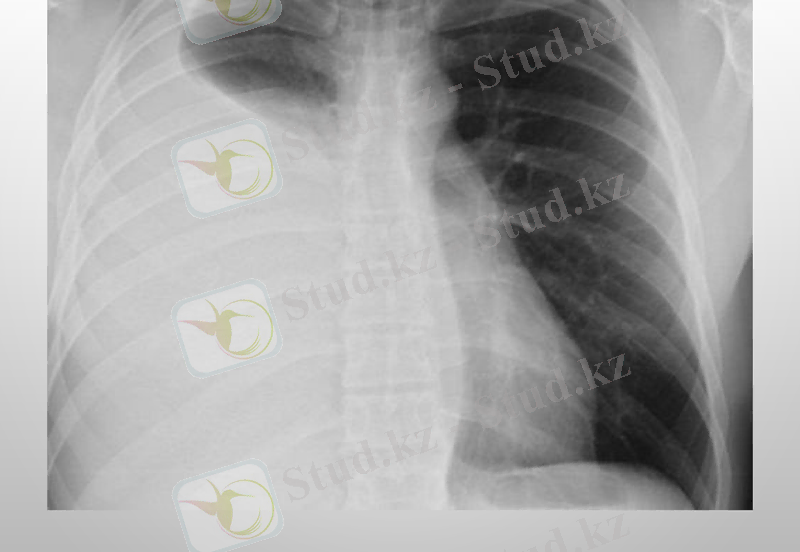

Плеврит - плевра қуысында сұйықтықтың жиналуы. Плевра - көкіректің ішкі бетін астарлап жататын сірі қабық.

Плевритті шартты түрде құрғақ (фибринозды) және іріңдік (экссудативті) деп бөледі. Құрғақ Плеврит кезінде сірлі қабық ісініп, қалыңдайды да қабыну процесі басталады. Ал іріңдік Плевритте плевра қуысы қан, ірің аралас сұйықтыққа толып кетеді. Адамда туберкулезді Плеврит жиі кездеседі. Плевриттің бұл түрі өкпеде немесе лимфа түйіндерінде басталып, кейін өкпені түгел қабындырады. Науқастың дене қызуы көтеріліп, құрғақ жөтел пайда болады.

Плевриттің диагностикасында рентгенография рентгеноскопии кеуде жасушаларының, плевральді қуыста УЗИ, плевральді пункции, диагностикалық торакоскопия жасалынады.

Туберкулезді плеврит